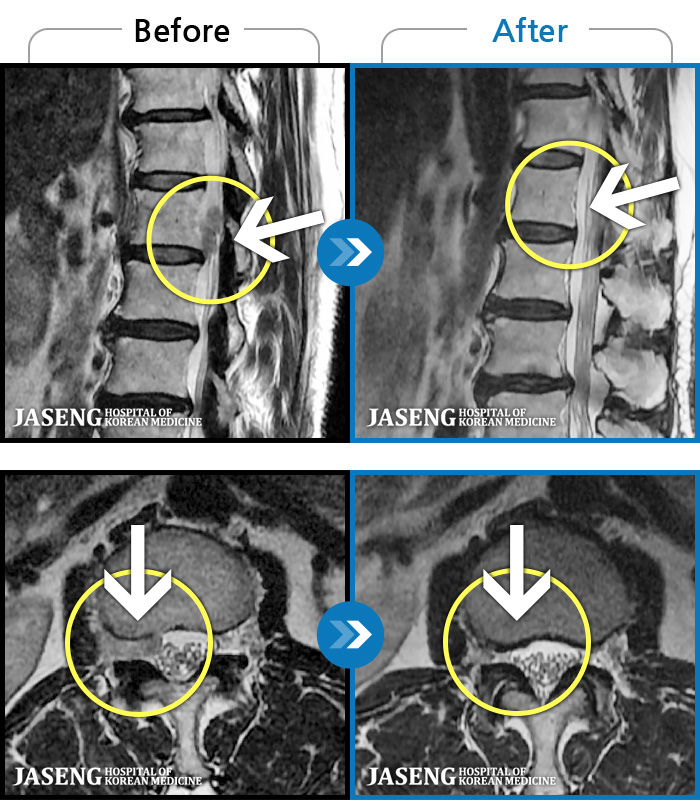

1,228건의 MRI 전후 사진으로 터진 디스크 흡수 사례를 확인하세요.

※ 환자분에게 사전 동의를 받아 동일 조건에서 촬영되었으며, 개인에 따라 치료 후 부작용이 발생할 수도 있으니 사전에 의료진과 상담 후 치료를 진행하시기 바랍니다.